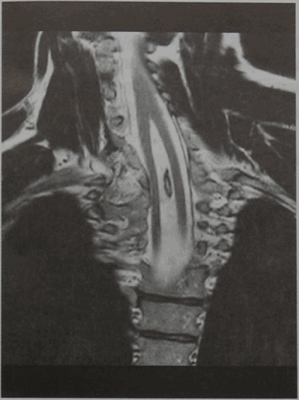

Пациент 25 лет, страдающий с детства сколиозом, который проявляется нарастающими нарушениями чувствительности и слабостью в правой руке на фоне опоясывающей боли. МРТ шейно-грудного отдела позвоночника (фронтальная проекция, Т2-взвешенное изображение). Две суженных половины спинного мозга разделены костной перегородкой (тип I - диастематомиелия с перегородкой).